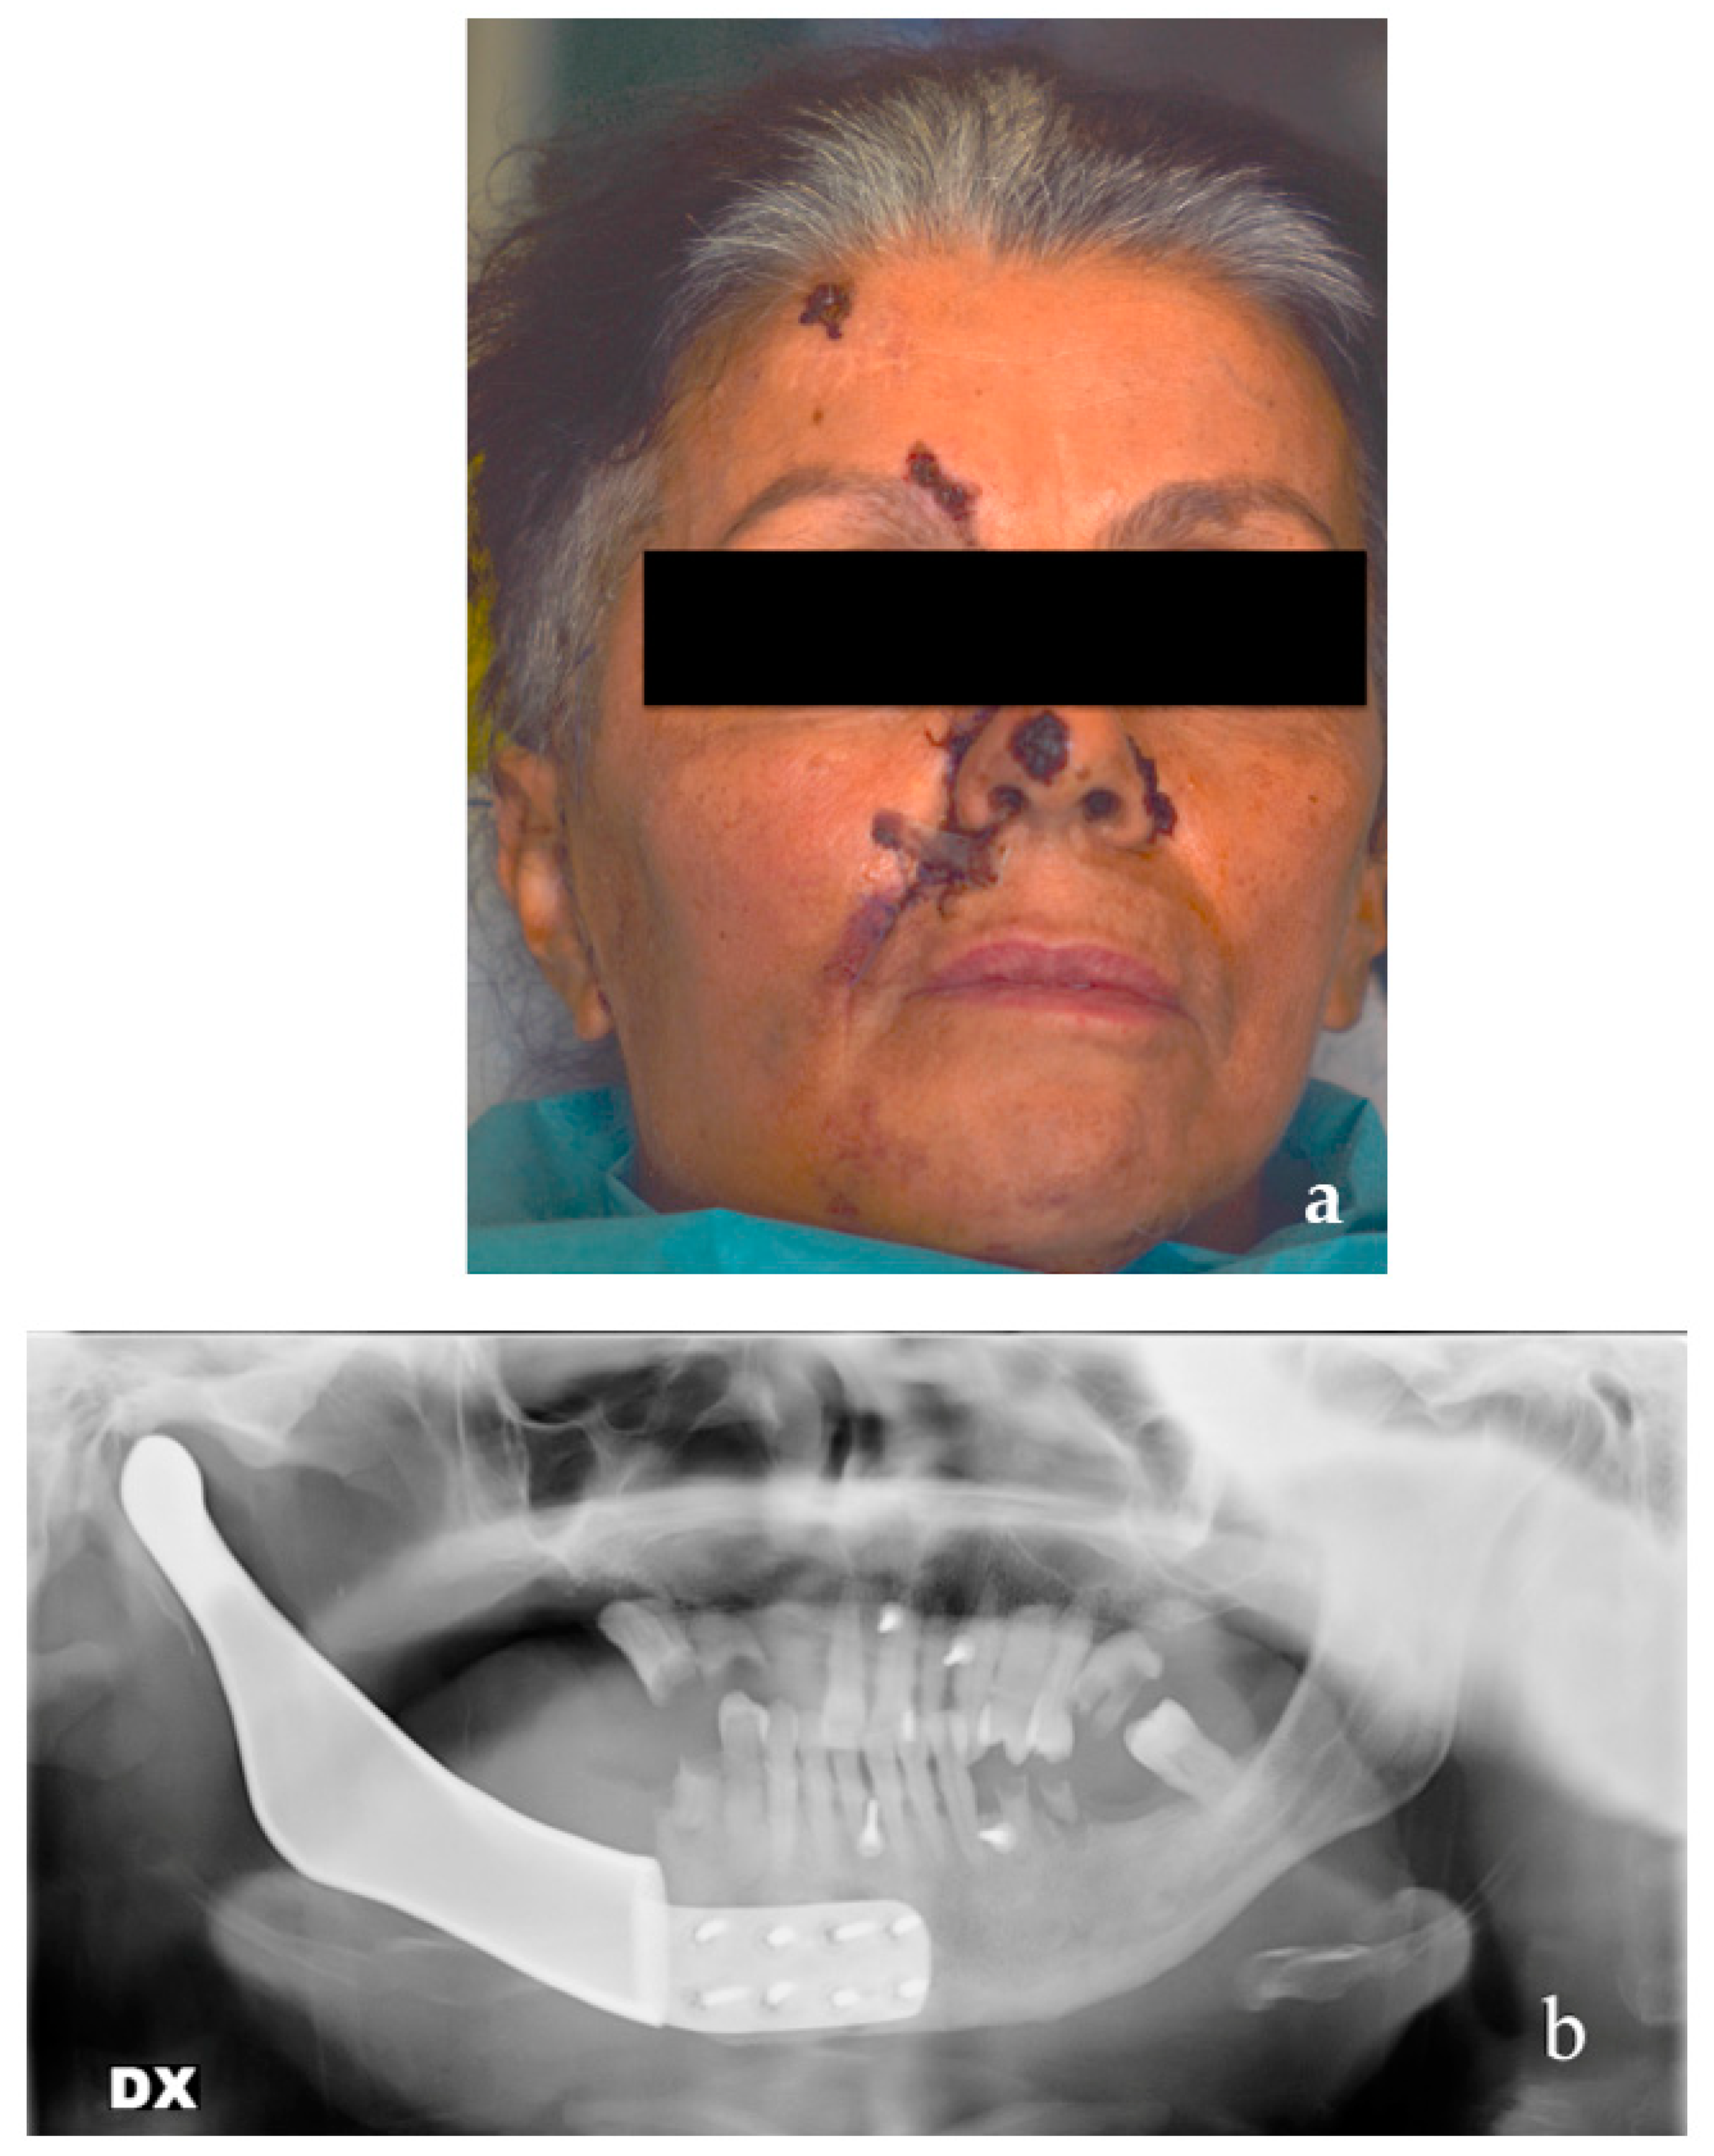

2.6. Patient #2

- Cortese, A.; Caggiano, M.; Carlino, F.; Pantaleo, G. Zygomatic fractures: Technical modifications for better aesthetic and functional results in older patients. Int. J. Surg. 2016, 33 (Suppl. 1), S9–S15. [Google Scholar] [CrossRef]